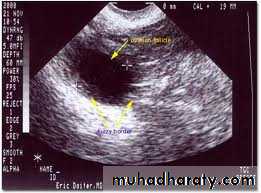

Medical applicationClinical assessment ovulation